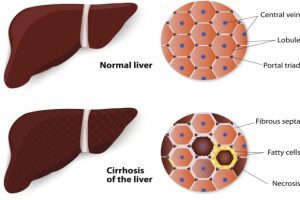

Liver fibrosis or liver scarring is a common cause of liver cirrhosis that experts now say could potentially be prevented with a drug normally used to help prevent allergies and asthma.

At least 30 million Americans have some form of liver disease. Some of these people suffer from liver fibrosis, which is the excessive buildup of scar tissue that can occur when inflammation and liver cell death occurs in many different types of chronic liver diseases. The liver scars when abnormal areas of cells form as dying liver cells are replaced by regenerating cells. Continue reading…

Hepatitis C infection in liver cirrhosis patients can be cured with investigational oral therapy. An advanced form of liver disease, cirrhosis can be caused by hepatitis C infection, alcoholism, autoimmune disease, and other strains of hepatitis, among other causes. Hepatitis C attacks the liver, leading to the formation of scar tissue.

In its early stages, damage caused by hepatitis C to the liver is referred to as fibrosis. As liver damage progresses, the damage becomes irreversible and is known as cirrhosis.

Cirrhosis of the liver is when the liver starts deteriorating to the point that it is unable to function normally. Healthy tissue is replaced by scar tissue, blocking the blood flow. Cirrhosis of the liver is irreversible.

The liver is the only organ that can regenerate itself, but if scarring is severe, it is unable to heal, so it deteriorates over time. As cirrhosis gets worse, the liver failure sets in. Continue reading…